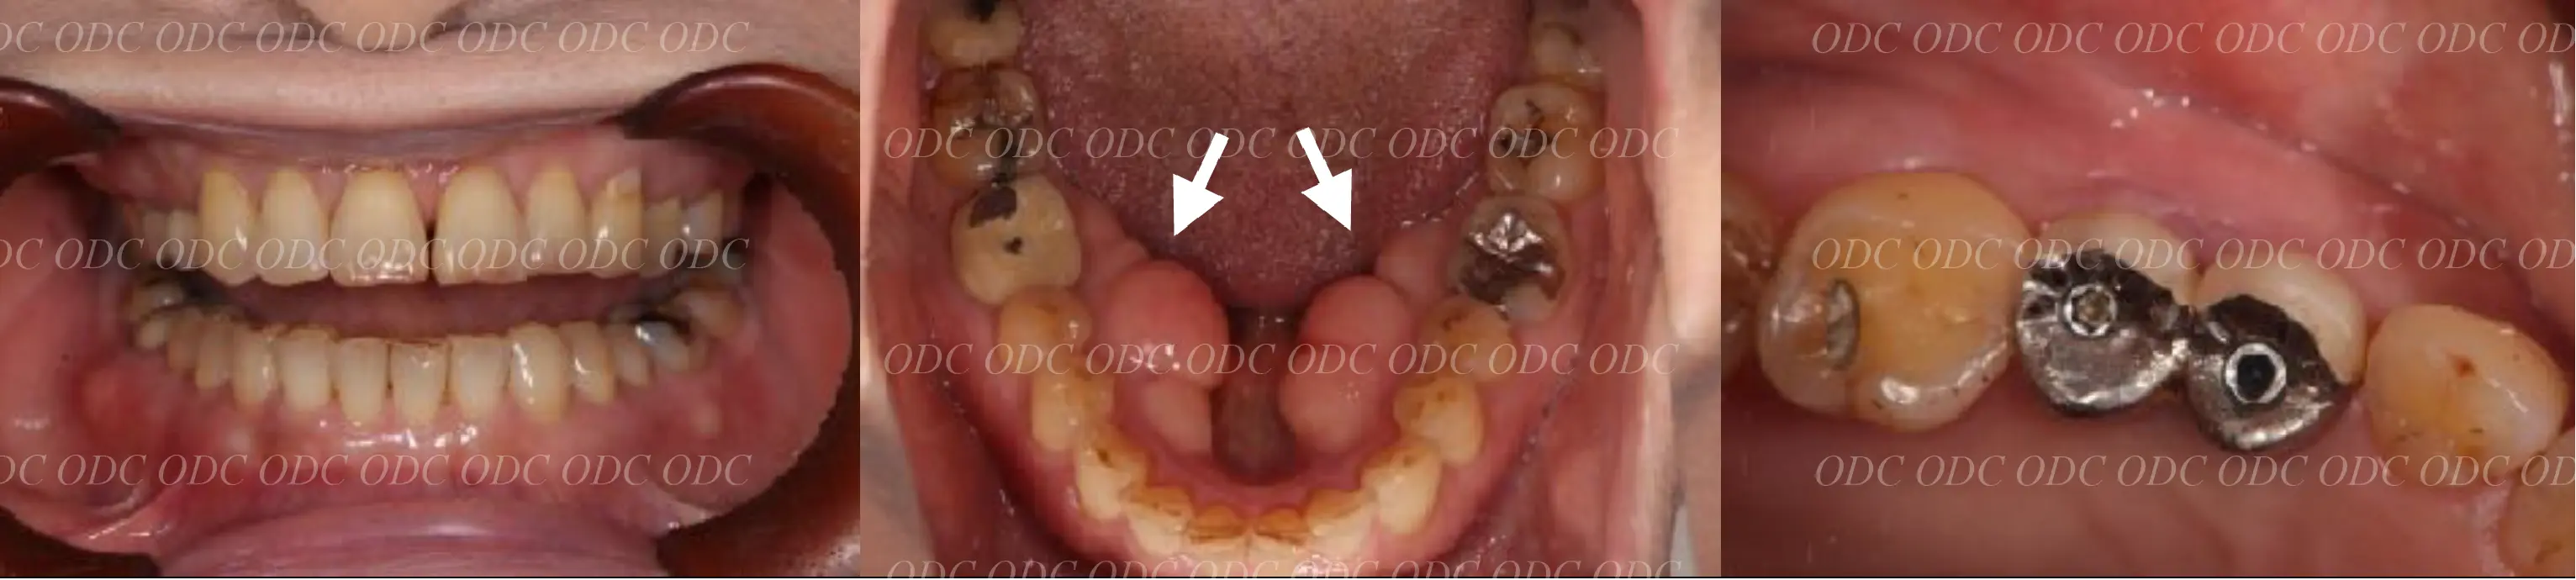

2011年、噛めないという主訴で65歳の男性が来院されました。

全顎的な治療を希望されていましたので、口腔内はもちろん骨格・顔貌・顎関節の診断を行い治療目標を設定致しました。

上顎天然歯に関しては矯正治療、下顎にはフルマウスのインプラント治療を計画致しました。

顎関節の安定を確認した後、矯正治療とインプラント治療を並行して行いました。

約3年の治療期間を経て、計画通りの満足のいく結果を獲得することができました。

2014年、治療終了時の口腔内の状態です。

インプラント上部構造はCADCAMによって作成されたジルコニアの上部構造です。

2024年、治療終了後約10年が経過いたしました。

顎関節を考慮した包括的な治療を行うことで咬合状態(噛み合わせ)は現在もとても安定した状態です。